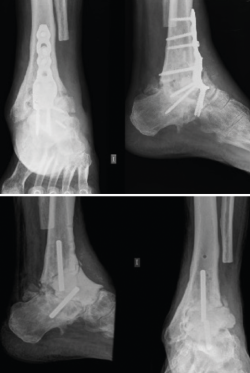

Para ejemplificar la aplicabilidad de la tecnología 3D, expondremos en este capítulo un caso realizado por los autores. Se trata de un enfermo de 63 años que consulta por infección crónica del tobillo izquierdo. Presentaba antecedentes de 10 cirugías previas en dicho tobillo. En el momento de la consulta, era portador de una placa de osteosíntesis con tornillos (Figura 1) y presentaba dos fístulas productivas.

Figura 1. Arriba: radiografía con pseudoartrosis séptica con placa anterior; abajo: radiografía tras retirada de la placa y con espaciador de cemento con tetones.